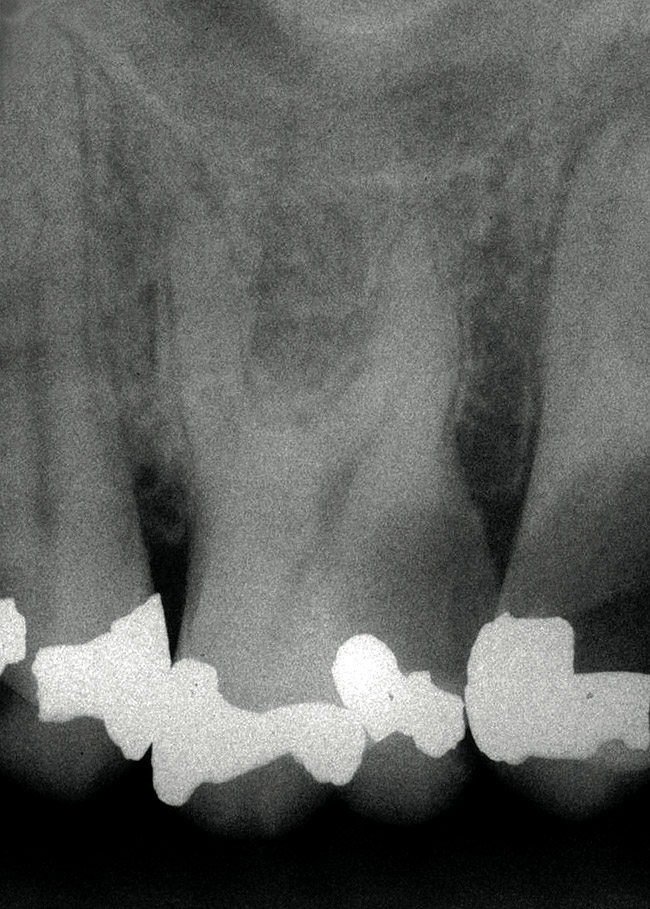

Figure 1 shows a radiograph of a typical maxillary first molar. Upon extraction, the apical anatomy was immediately studied and photographed under a global microscope ( Figure 2, Figure 3, Figure 4, Figure 5 and Figure 6). That is a take-home lesson; the extracted teeth should be studied with loupes or microscopes. These photographs demonstrate an important lesson. The two-dimensional radiograph shows three roots. In reality, however, a significant percentage of maxillary first and third molars—80% in some studies—have four roots and four or more canals. 1,2 While the MB and MP (MB-2) roots are usually fused, their morphology is unique. For diagnostic, access, and shaping purposes, it is safer to think of them as separate roots. Wisdom teeth often exaggerate the anatomic features of first and second molars, and a significant percentage of maxillary third molars have four distinct roots. The author's personal bias is to consider most maxillary first the radiographic apex of the tooth. The use of the radiographic root apex for use as the reference point for measuring the apical extent of the root filling is the common standard, yet has been criticized because of the poor correlation between the location of this point and the actual canal foramen. 5 The illustrations used in advertising and manufacturer's "tip cards" only further the notion of simple foramen anatomy. While simple anatomy is often the case with incisor teeth, a quick perusal of the posterior teeth in Brown and Herbransen's Dental Anatomy & 3D Interactive Tooth Atlas demonstrates that a significant portion of the foramen exit short of the apex and have multiple foramina. 6 The same extracted tooth in Figure 2 demonstrates that the palatal foramen is more than a millimeter short of the radiographic apex. If this tooth were filled to the constriction, which for arguments sake is 0.75 mm from the foramen, a straight-on radiograph would depict the fill as being at least 2 mm "short."